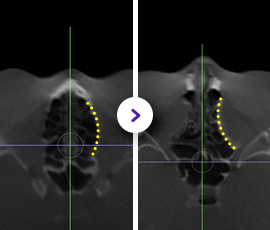

使用专用设

备进行精细截骨

(包括眼眶内壁、下壁、侧壁) -

将截骨部位

向内推移,

扩大眼眶空间 -